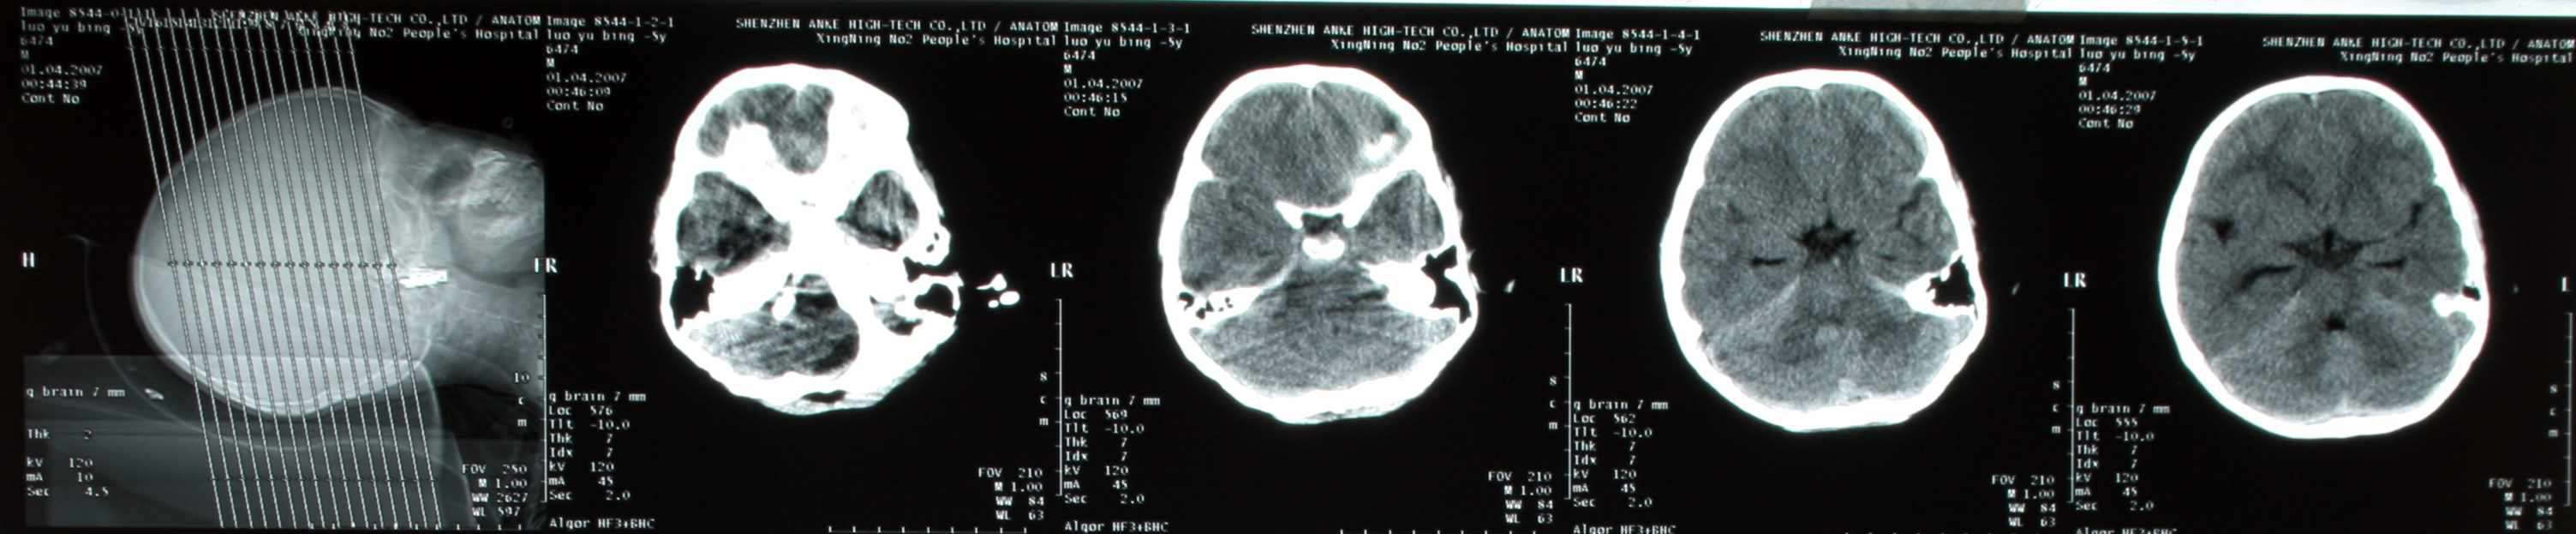

患儿,男,3周岁,半小时前不慎从床上摔下来,当时前额着地,后诉有点痛,伴呕吐二次,请各位老师会诊,患儿头颅有没有问题,后枕部颅下密度增高影,是伪影还是有出血,请指点:

图处箭头示的地方是出血吗,请指点